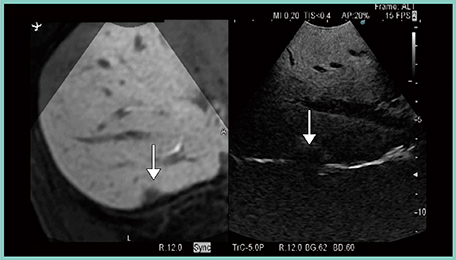

症例3は,大腸がん肝転移の化学療法後の症例である。前上区(S8)に大きな腫瘍,S7に小さな腫瘍があるが,化学療法後に腫瘍が縮小したため,術中エコーにてS7の腫瘍が確認できず,RVSを施行した。しかし,化学療法によって腫瘍が著明に縮小していたため,造影MR画像との同期表示でも確認できず,造影超音波を施行しても腫瘍を見つけることができなかった。そこで,再度RVSに立ち返り,触診を行いながら造影MR画像と造影超音波画像を同期表示したところ,径6mmの腫瘍が確認できた(図4)。

図4 症例3:大腸がん肝転移(↓)の化学療法後の症例(腫瘍の同定)